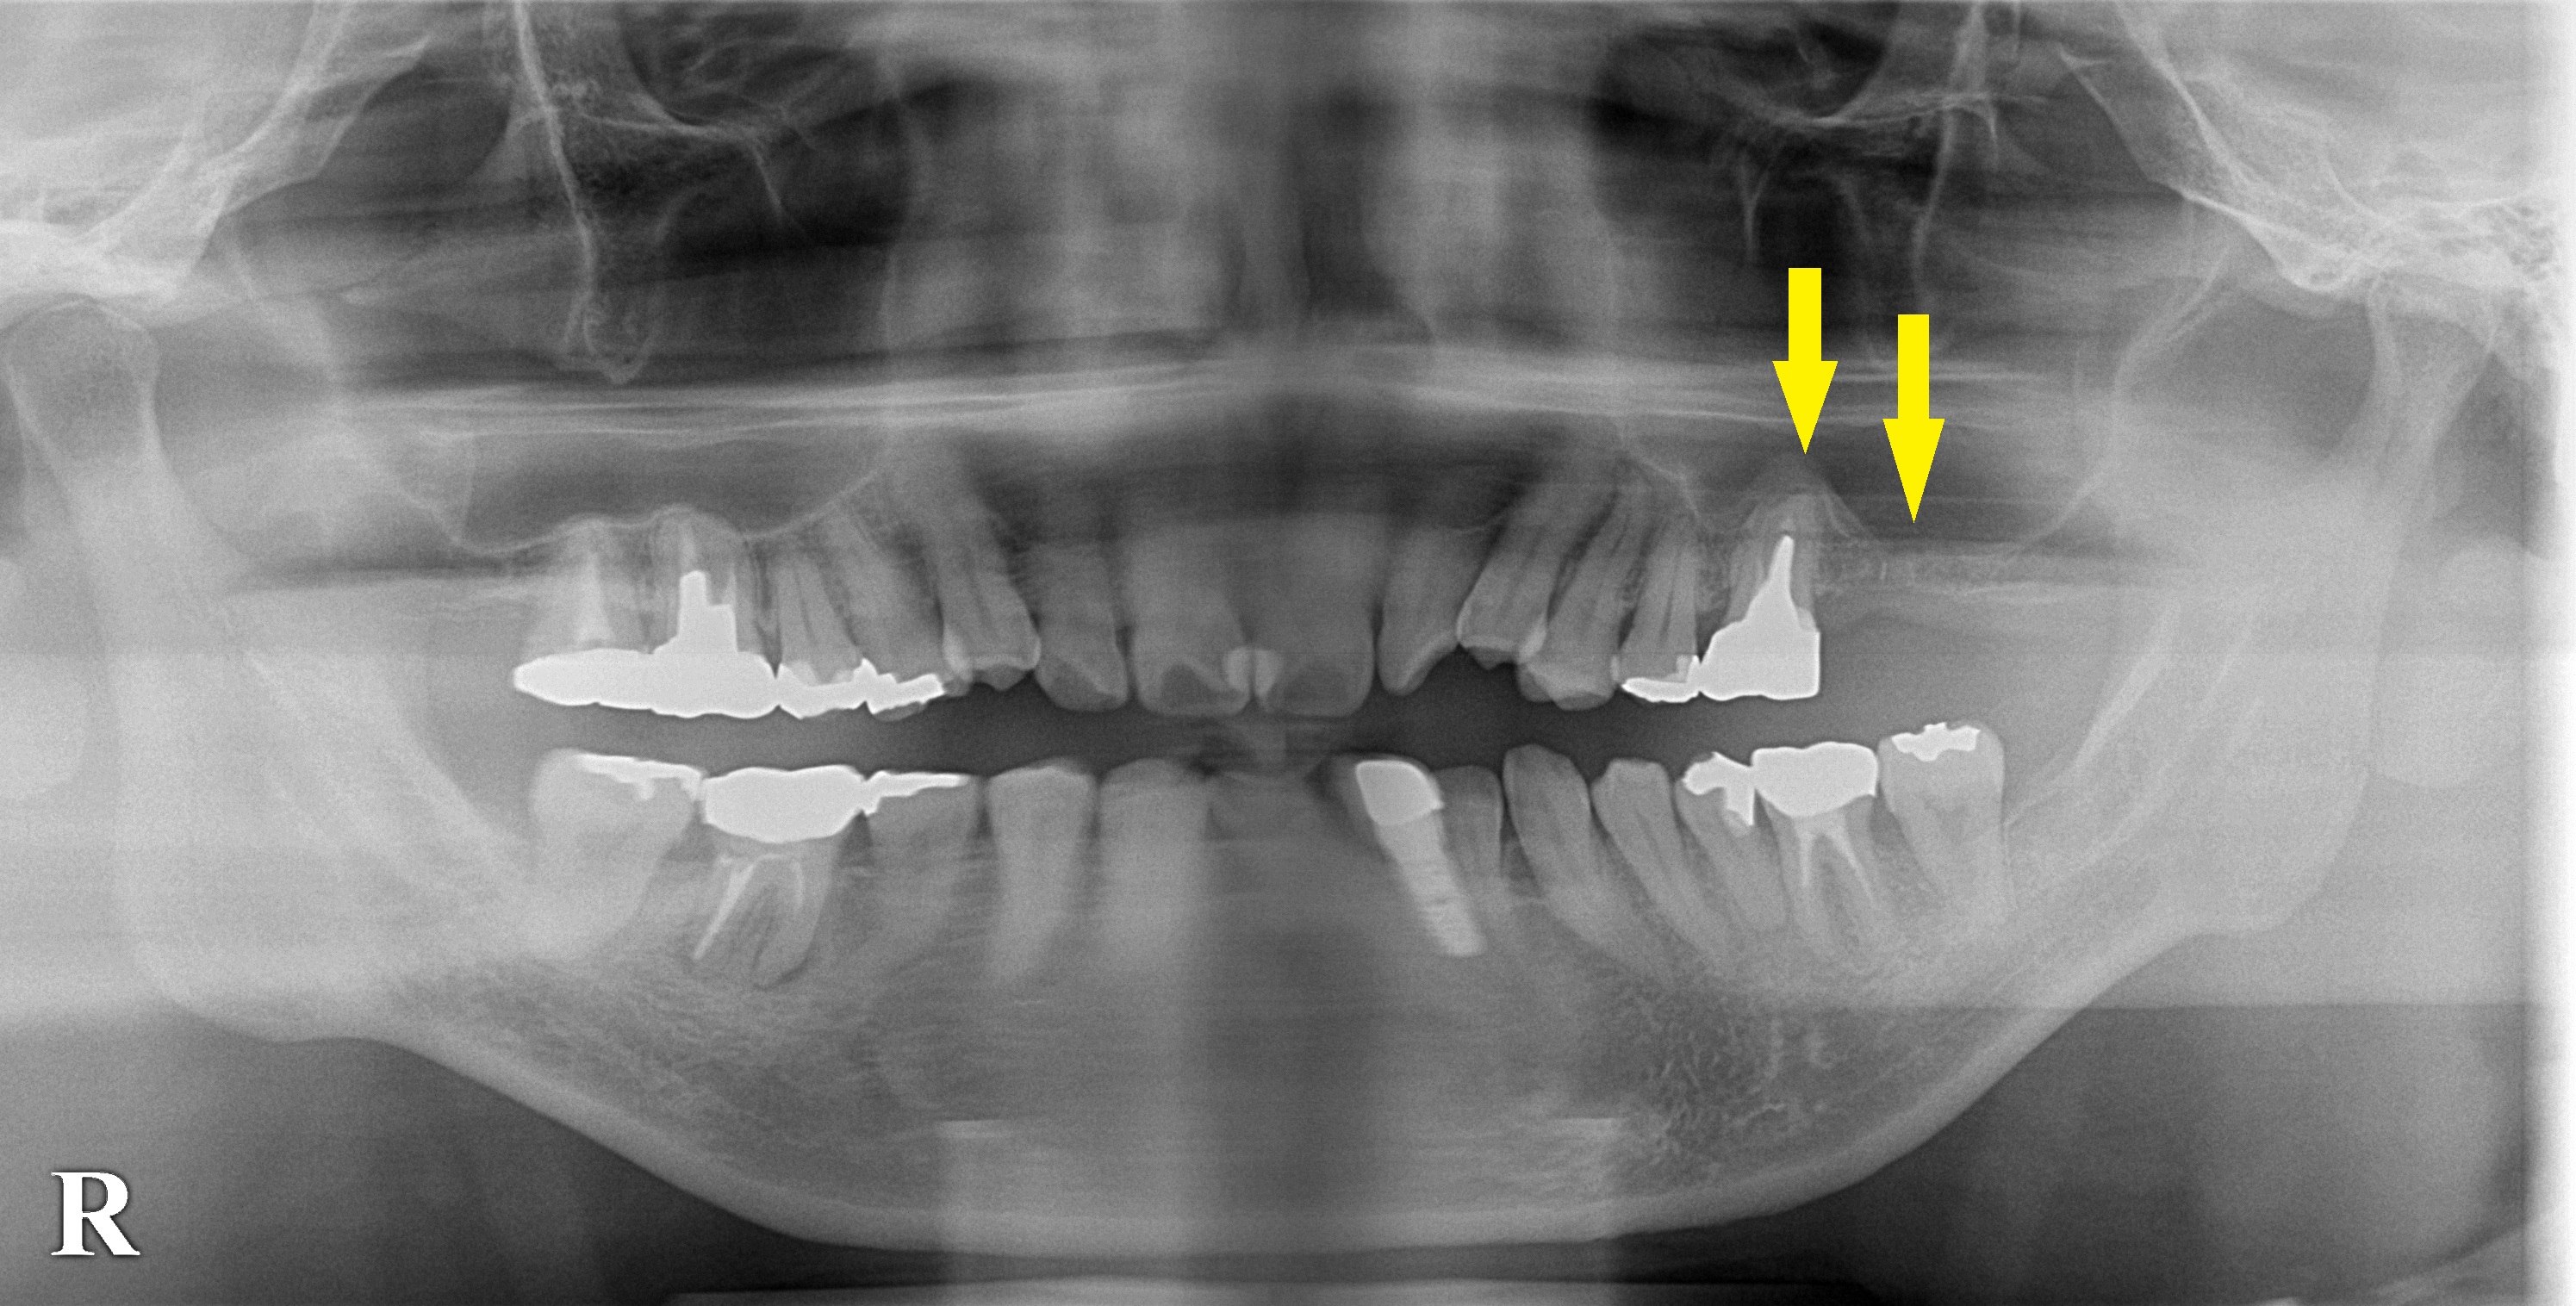

レントゲン写真で、抜歯が必要な左上顎第一大臼歯と、その後ろの第二大臼歯部分は骨がかなり薄くなってしまっています。

そこで、まず、第一大臼歯を抜歯し、サイナスリフトという骨造成術を行なってから、インプラント埋入術をすることとなりました。